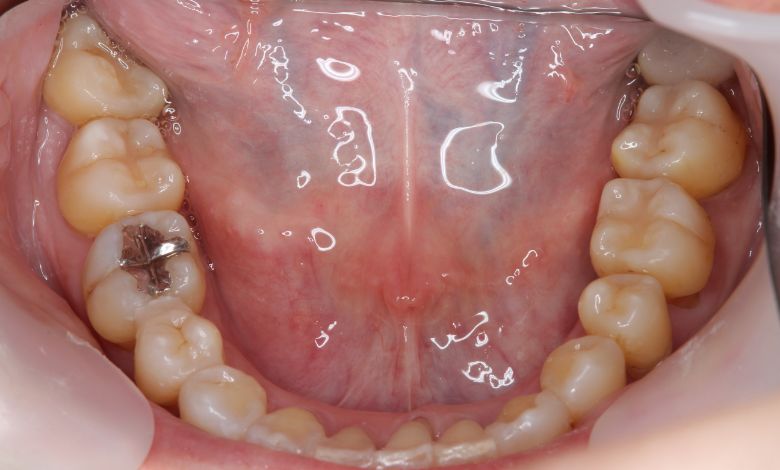

下顎の歯列では、前歯部に強い重なりが見られ、中切歯および側切歯がねじれたり前後にずれて生えているのが確認できる

術前に認められた前歯3本の強い重なりは完全に解消され、スムーズな歯列が形成されました。

精密検査の結果、抜歯を行わずに歯列弓を拡大する治療方針を選択。歯が正しい位置に並ぶスペースを

確保したことで、歯列は自然なU字型に整い、叢生が解消されました。見た目の改善だけでなく、

咀嚼機能の向上や清掃性の改善といった機能面での効果も期待できます。